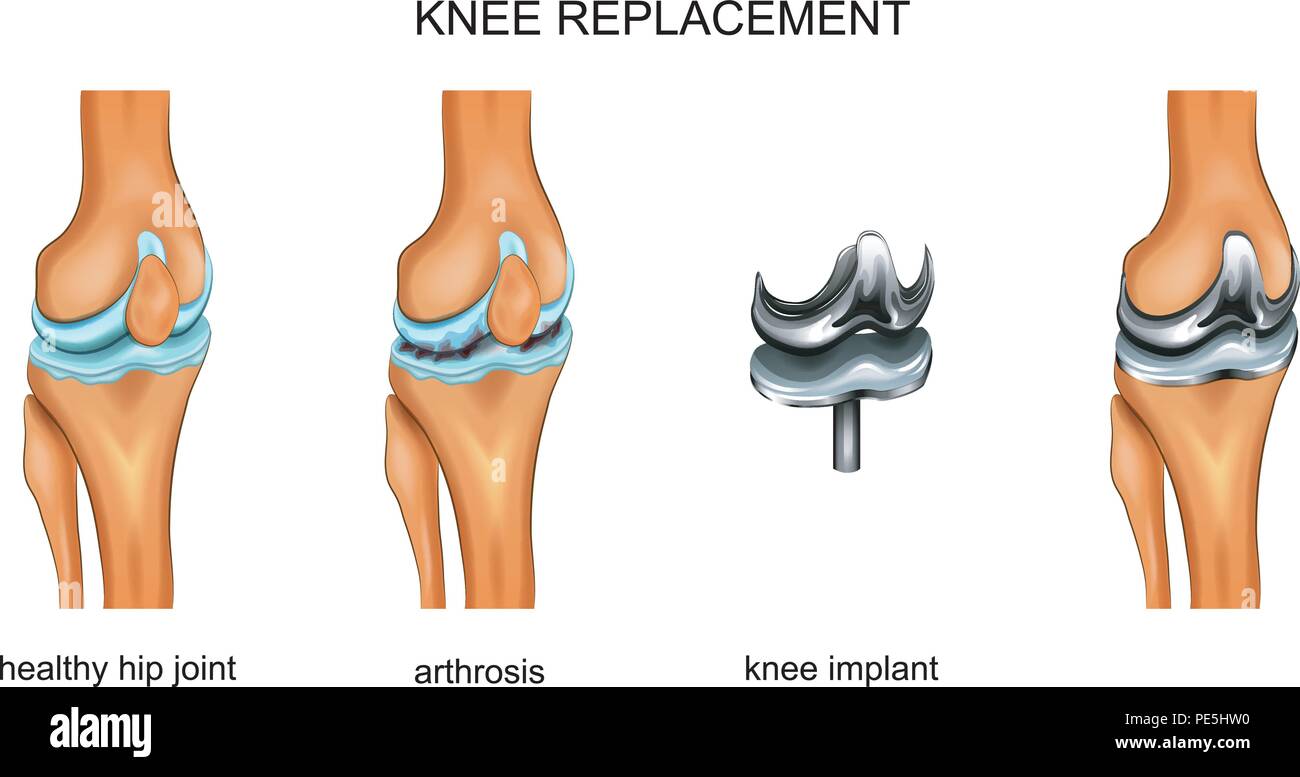

vector illustration of a total knee replacement Stock Vectorhttps://www.alamy.com/image-license-details/?v=1https://www.alamy.com/vector-illustration-of-a-total-knee-replacement-image215253388.html

vector illustration of a total knee replacement Stock Vectorhttps://www.alamy.com/image-license-details/?v=1https://www.alamy.com/vector-illustration-of-a-total-knee-replacement-image215253388.htmlRFPE5HW0–vector illustration of a total knee replacement